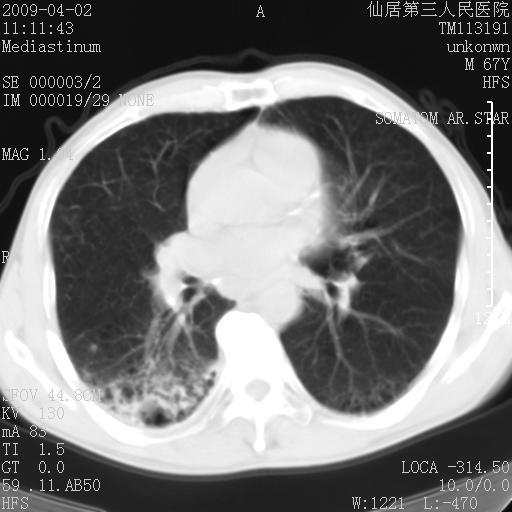

患者老年男性,乏力畏寒来诊,摄胸片示右下肺感染性病变,抗炎两周后复查胸片,无好转有进展。

后做ct平扫表现如下:

考虑右肺炎症可能性大,不除外细支气管肺泡癌

是否还要考虑肺间质纤维化,建议hrct扫描。

病灶呈蜂窝征,纵隔多个淋巴结肿大;肺泡癌需考虑

右肺下叶背段干酪性肺炎。请痰检[emb28]

我认为普通的感染应该可以除外,间质性肺炎可能性较大,但如何解释纵膈的淋巴结肿大呢

考虑双肺间质性改变(间质纤维化?)伴右肺下叶感染。